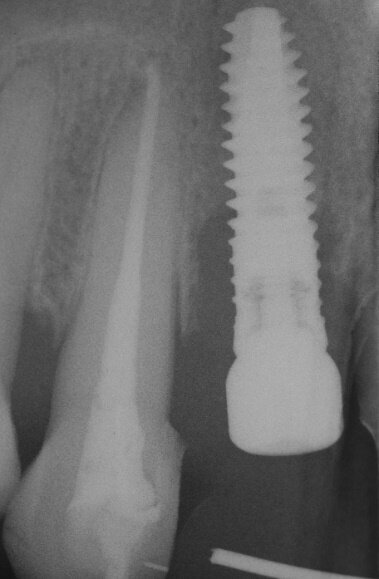

La fase chirurgica viene pianificata con la preparazione iniziale (igiene orale, controllo emato-chimico delle condizioni della paziente, prescrizione della profilassi/terapia antibiotica19-20 e della sospensione del fumo). Il 23 giugno 2011, vengono estratti i due incisivi laterali (Figg. 13, 14) e inseriti contestualmente due impianti Xive (Dentsply) di diametro 3,8 mm e lunghezza 15 mm (Figg. 15, 16), dimensioni ottimali per la successiva protesi (ponte di 4 elementi da 1.2 a 2.2 con 1.1 e 2.1, elementi “intermedi”).

Vengono inserite due viti di guarigione e riposizionato il provvisorio, debitamente adattato in corrispondenza dei due incisivi laterali. Alla seduta di controllo a una settimana dall’intervento implantare, la paziente confida, alle assistenti dello studio, di non aver assunto gli antibiotici prescritti né prima né dopo l’inserimento degli impianti e tantomeno di essersi astenuta o limitata dal fumo di sigarette! Alla seconda visita di controllo, dopo 30 giorni, la stessa presenta un pessimo stato di igiene orale e due ascessi vestibolarmente ai due impianti (1.2 e 2.2) (Figg. 17, 18).